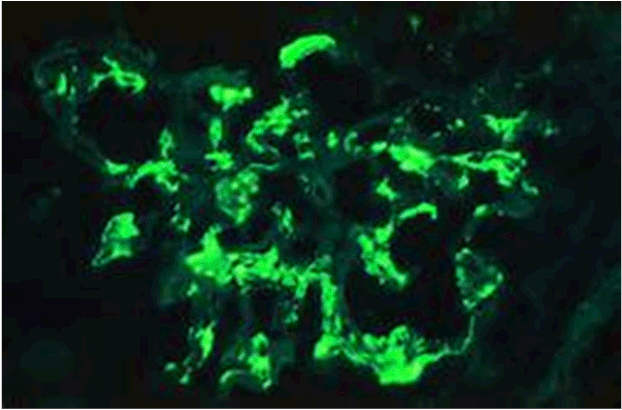

The patient was asymptomatic with normal vital signs (pulse 78/min, BP 132/78 mmHg, RR 18/min, temperature 37◦C) and in stable general condition. He had a history of controlled type 2 diabetes mellitus for 10 years (HbA1c 7%) and hypertension for 3 years, but there was no past history of renal disease or family history of kidney disease. There was no recent systemic viral or bacterial infection, no recent blood or fluid loss, and no recent exposure to nephrotoxic drugs or radiocontrast agents. Funduscopic examination revealed no diabetic or hypertensive retinopathy. Ultrasound examination showed normal size kidneys with no focal dilated collecting system and no significant post-residual urine volume. His initial urine analysis showed RBCs 3-4/hpf and albumin was +++. Serum creatinine was 4.5 mg/dl (eGFR 14 ml/min) and proteinuria 400 mg/24hour urine collection. Serum IgA level was within normal range (68-432 mg/dl). His serology reports revealed negative ANA, anti-DNA, ANCA, and anti-GBM antibody, but slightly decreased C3 and normal levels of C4. Immunoglobulins and cryogolbulins were within normal limits, HBsAg, antibodies to HCV and HIV were all negative. Repeated urine analysis showed 25 pus cells, 3+ proteinuria and many RBCs/hpf. The pus cells, and RBCs, indicated urinary tract infection, possibly due to Foley’s catheterisation. Urine culture and sensitivity revealed Proteus bacterial growth which was sensitive to imepenem. Repeated urine analysis showed no pus cells and urine culture showed no growth following treatment with a course of imepenem. His blood pressure was controlled (127/78 mmHg) with angiotensin converting enzyme inhibitor (Perindopril 5mg OD). The sudden, rapid and unexplained deterioration in renal function, and the absence of diabetic and hypertensive retinopathy, the decision for a diagnostic renal biopsy was taken. The patient was bed-bound due to fixed flexion deformities of lower limbs and deformity of left arm, and it was difficult to perform a renal biopsy in a suitable position. However, a week later and under effect of sedation, a real time renal biopsy was performed in right lateral position under ultrasound guidance. Post-procedural condition of the patient was uneventful. Light microscopy showed 32 glomeruli with prominent mesangial proliferation, fibrocellular crescent formation in 4 glomeruli, 2 glomeruli were sclerosed, and there was moderate degree of interstitial inflammation and tubular atrophy (Figure 1a and 1b). The immunofluorescent stained sections showed focal mesangial and capillary wall deposits for IgA and C3 (Figure 2).

Figure 2. Immunofluorescent stained sections showed focal mesangial and capillary wall deposits for IgA.

Primary glomerulonephritis, such as IgA nephropathy, has been reported to be superimposed on a background of diabetic glomerulosclerosis in patients with type 1 and 2 diabetes mellitus [25,26].  This could be a possibility in this reported case, though patient’s diabetes mellitus was well-controlled (HbA1c 7%, no proteinuria, normal renal function and no diabetic retinopathy). Furthermore, histologic evaluation disclosed prominent mesangial proliferation, interstitial inflammation and tubular atrophy, but not the presence of thickened glomerular basement membranes or nodular sclerosis. The histology also revealed four glomeruli with fibrocellular crescent formation but only two with glomerulosclerosis (out of 32 glomeruli). The immunofluorescence studies showed focal mesangial and capillary wall deposits for IgA and C3.